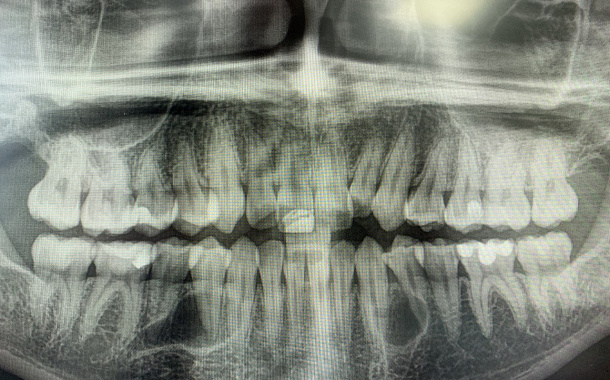

Применение Indiba после стоматологических процедур, таких как удаление зубов, костная пластика и имплантация, обеспечивает ряд значительных преимуществ:

- Профилактика осложнений: активизация иммунных процессов снижает риск развития инфекций.

- Улучшение приживаемости имплантатов: усиление кровоснабжения в области имплантации способствует лучшей интеграции имплантата с костной тканью.